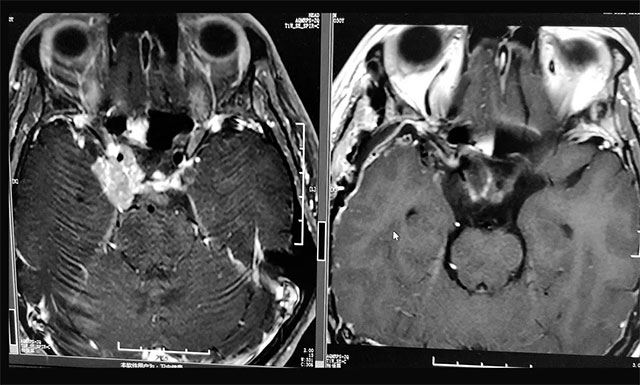

▲ 術(shù)后影像顯示殘余腫瘤被切除

在充分準(zhǔn)備并征得家屬同意后,李士其教授在吳治群博士、黃秀夫醫(yī)生協(xié)助下為患者行開顱手術(shù),經(jīng)翼點(diǎn)入路將殘余約2.5cm*2cm*2cm大小腫瘤切除。

術(shù)后第二天,患者視力已有明顯改觀,并能正常溝通交流,目前正在康復(fù)中,同時李士其教授叮囑患者出院后要注意定期復(fù)查。